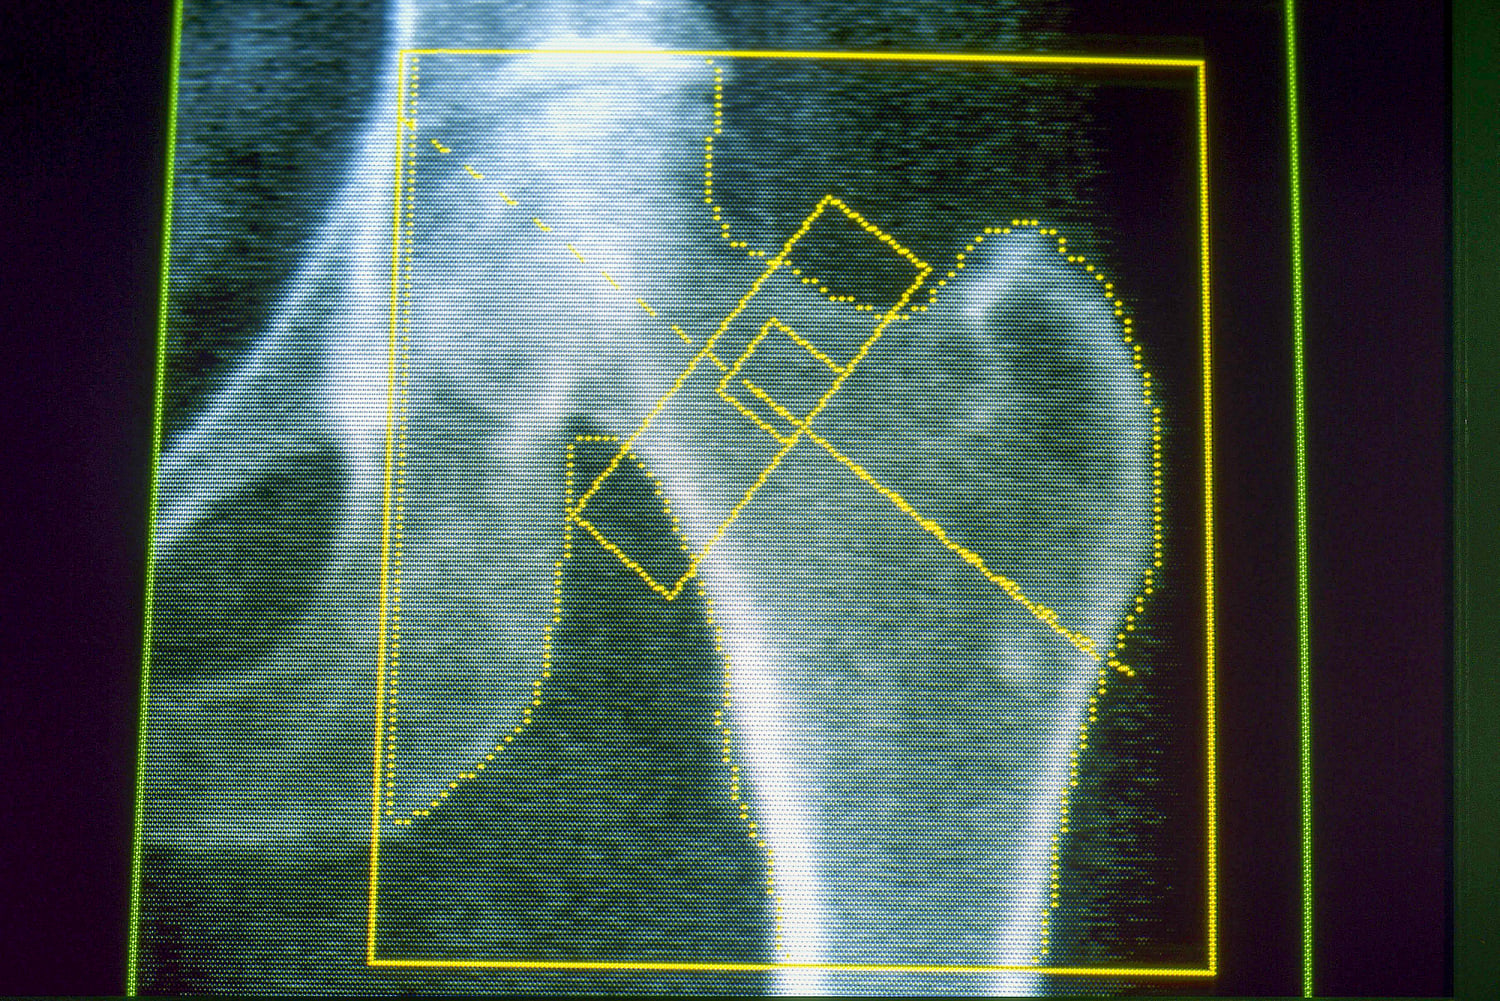

Osteoporosis is a disease that weakens the bones and makes them likelier to break or fracture, often from minor falls. It’s a common concern for many older adults and for people who lose a significant amount of weight over a short period of time. Gout, meanwhile, is a painful form of arthritis that can occur when the body has too much uric acid, which can come from a diet high in red meat and alcohol — as well as rapid weight loss.

About 4% of GLP-1 users developed osteoporosis, compared with a little over 3% of nonusers — an increased risk of about 30%. A related condition, osteomalacia, which involves the softening of the bones, was rare but also occurred about twice as often among people on GLP-1s.

Because the new research was observational, it can’t prove the medications caused either condition. Horneff said the team didn’t know about patients’ diet or exercise habits, or whether they were taking vitamin D supplements or other nutrients important for bone health. But the results echo other research, including a study published in February in the Journal of Clinical Endocrinology & Metabolism that linked GLP-1 drugs to a higher risk of osteoporosis-related fractures in older adults with Type 2 diabetes.